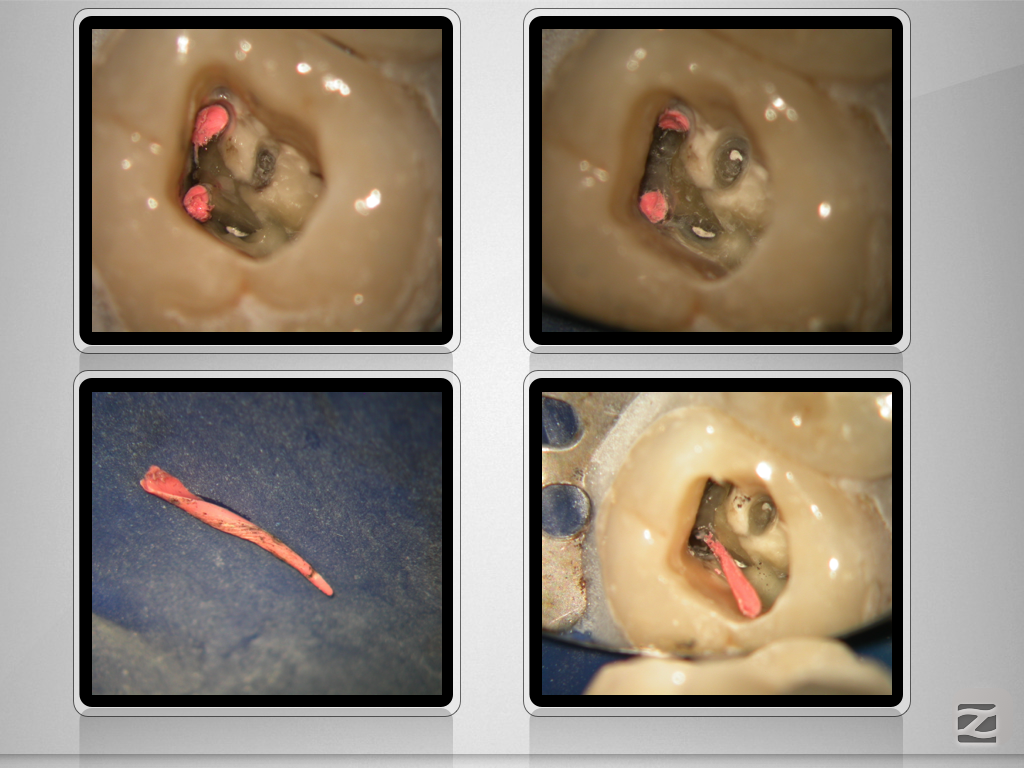

26D.010

X-Bein